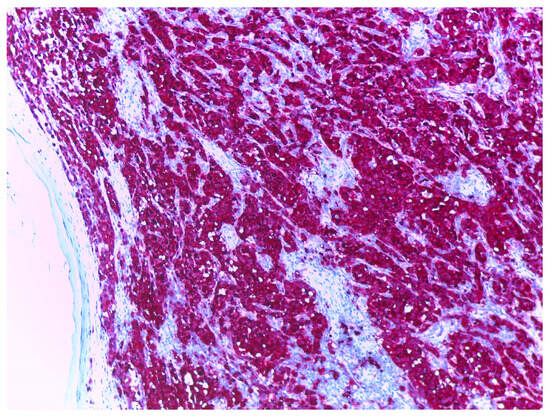

- Ronchi, A.; Cazzato, G.; Ingravallo, G.; D’Abbronzo, G.; Argenziano, G.; Moscarella, E.; Brancaccio, G.; Franco, R. PRAME Is an Effective Tool for the Diagnosis of Nevus-Associated Cutaneous Melanoma. Cancers 2024, 16, 278. [Google Scholar] [CrossRef] [PubMed]